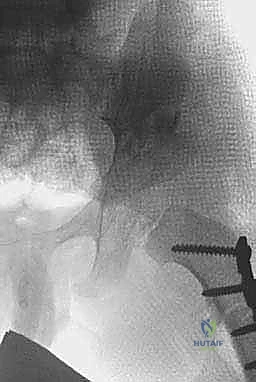

6. تثبيت المفصل وإغلاق الجرح:

يتم أخذ طعم عظمي من حوض المريض ووضعه في شق القطع العظمي لتثبيت السقف في وضعه الجديد. في بعض الحالات، قد تُستخدم دبابيس معدنية (K-wires) لتثبيت إضافي مؤقت. يتم إغلاق الجرح بخيوط تجميلية تذوب تلقائياً.